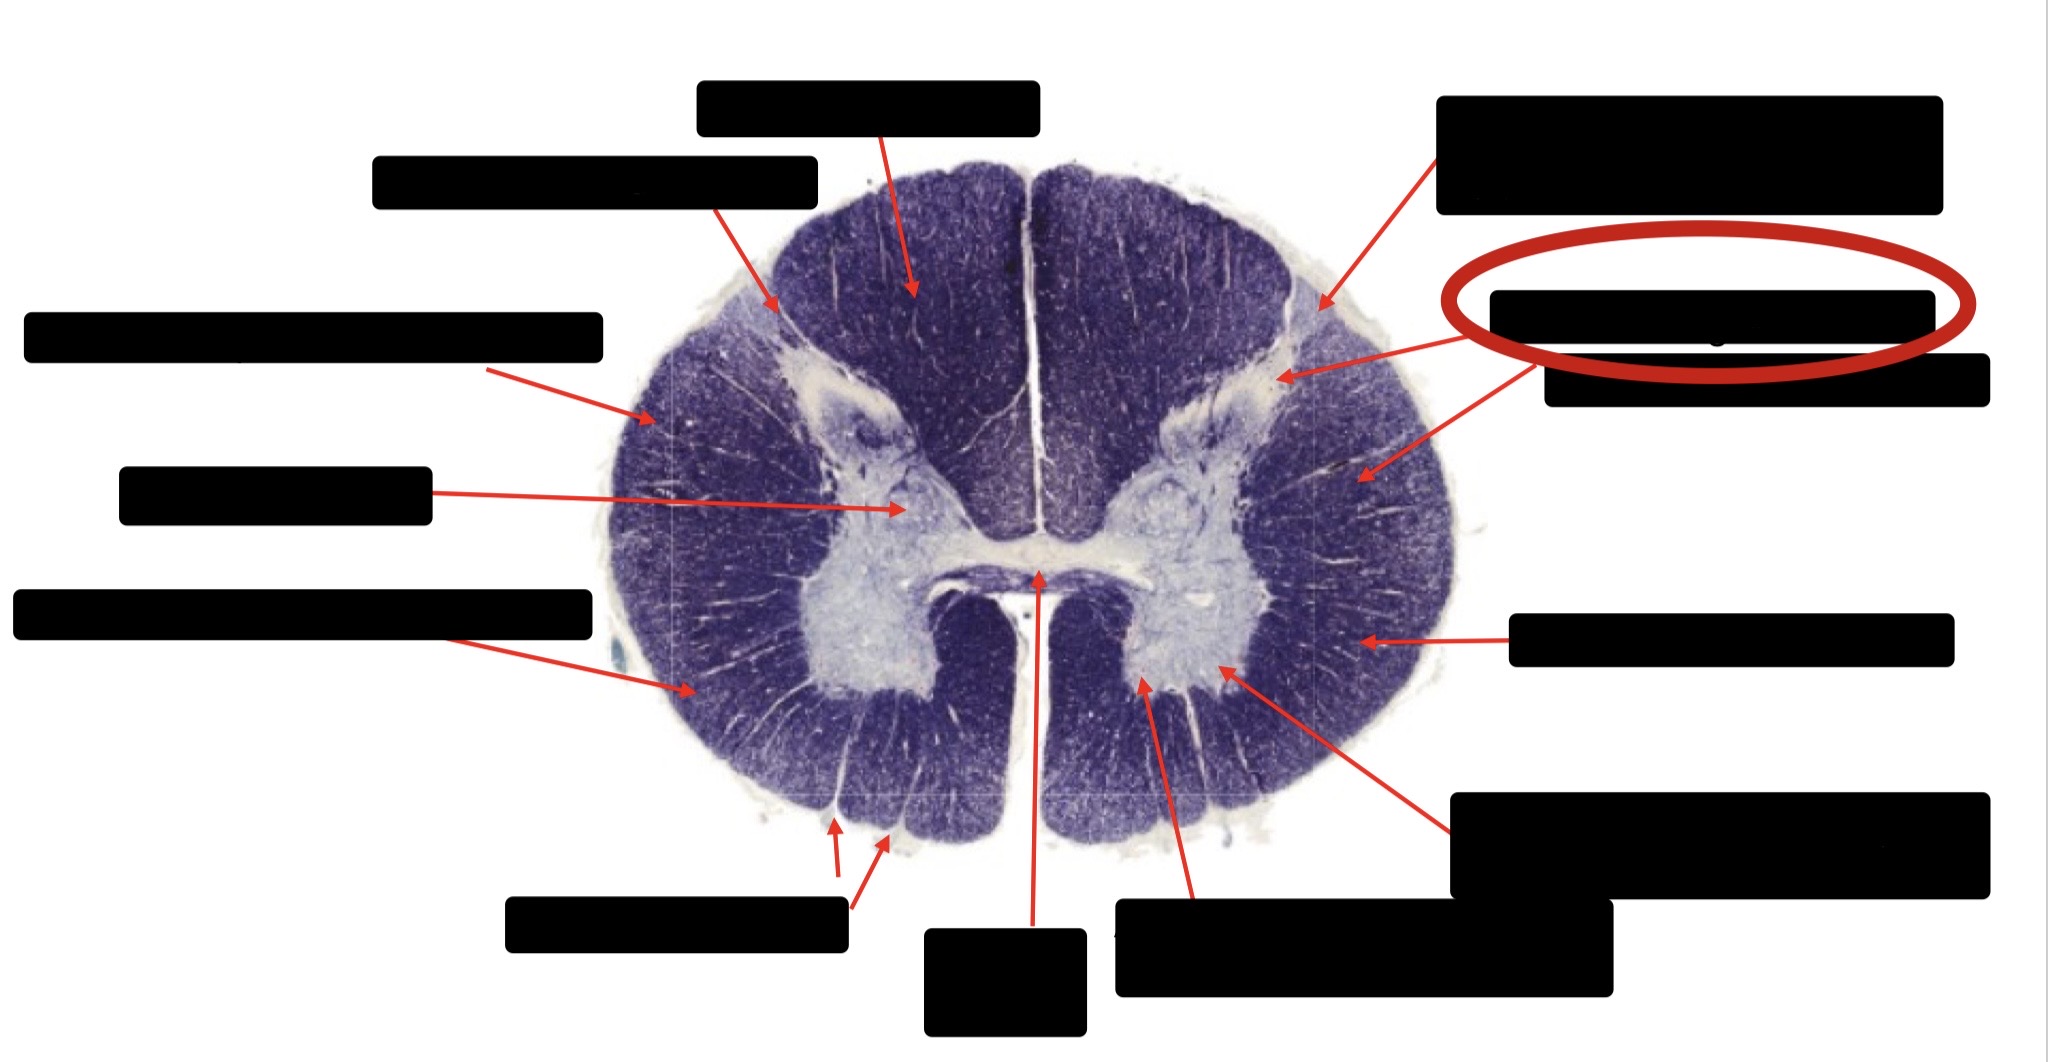

Central Canal

Anterior Corticospinal Tract

Posterior Column (Fasciculus Gracilis)

Posterior Column (Fasciculus Cuneatus)

Substantia Gelatinosa

Accessory Nerve Fibers

Anterior Horn Motor Fibers (Accessory Muscles)

Anterior Horn Motor Fibers (Proximal Muscles)

Ventral Root Fibers

Anterior Horn Motors Neurons (Proximal Muscles)

Posterior Columns (Joint Position, Vibration, Pressure)

Fasciculus Cuneatus

Fasciculus Gracilis

Dorsal Root

Dorsal Spinocerebellar Tract

Ventral Spinocerebellar Tract

Lateral Spinocerebellar Tract (Pain & Temperature)

Ventral Root

Anterior Horn (Motor Neurons)

Distal Limb Movements

Lateral Corticospinal (Pyramidal Tract)

Rubrospinal Tract

Axial & Proximal Limb Movements

Lateral Reticulospinal Tract

Vestibulospinal Tract

Ventral Reticulospinal Tract

Tectospinal Tract

Ventral Spinthalamic Tract (Pressure Touch - Minor Role)

Ventral (Uncrossed) Corticospinal Tract (Distal Limb Movements - Minor Role)